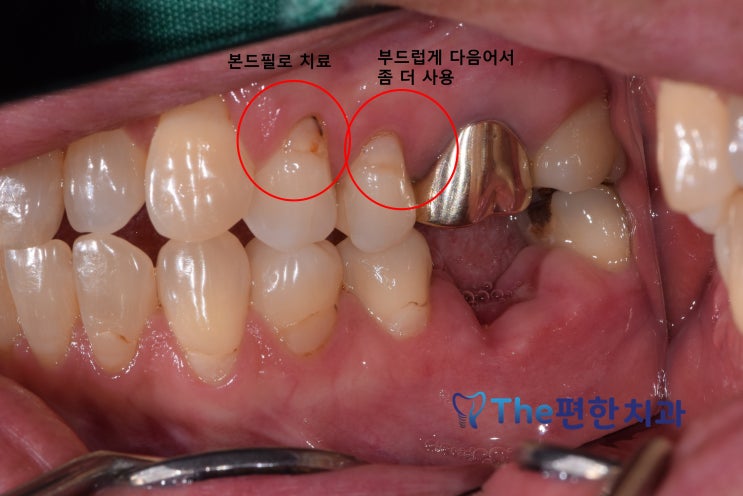

잇몸패임, 시림, 치경부 마모, 본드필